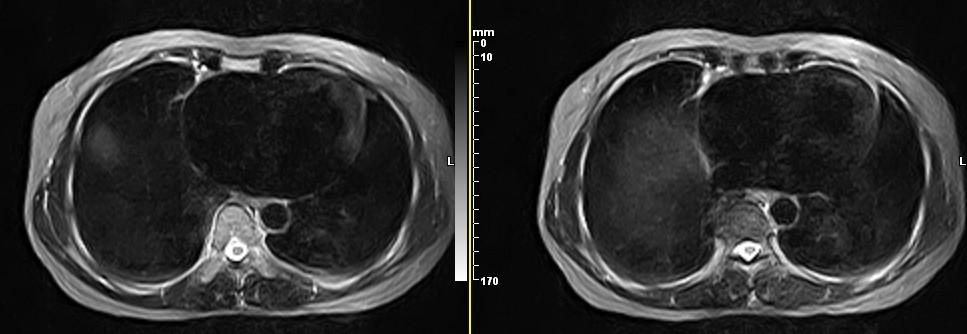

女,49岁。三年前因胸部不适在外院行CT检查诊断报告:右胸壁占位病变,考虑胸膜间皮瘤可能性大。现病人到我院检查了解情况。算是较典型的病变吧?大家看看MR比CT优点在哪里?

病检神经鞘瘤

病检是神经鞘瘤。

液性信号符合神经鞘瘤囊变。